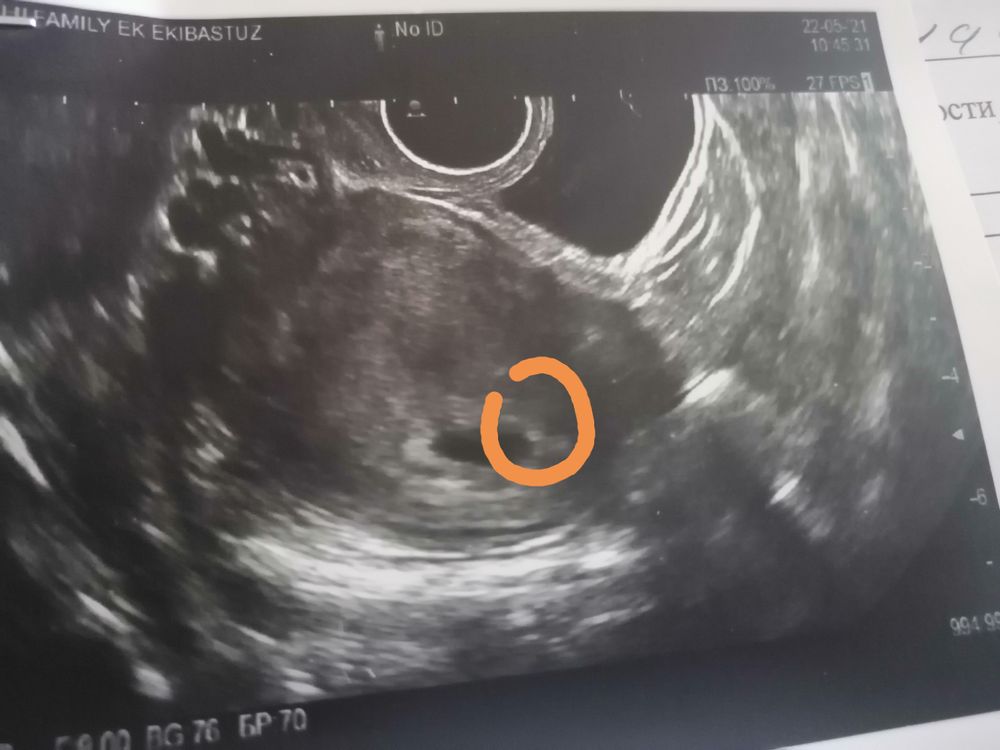

Узи 5 недель

Всем привет, последнии М 12.04. О не отслуживала, тест выдал призрака на примерно на 8дпо. Была на узи в 2 дня задержки, естественно ничего не увидели. Сегодня 10 дней задержки. Пошла к другому врачу. Написала Б 5 недель, я спросила эмбриона ещё нет, она говорит уже мешочек есть и эмбрион(показала на мониторе даже, ноя ничего толком не поняла) Но очень крошечные, приди через неделю, сейчас скину фото, это вот этот пузырёк справа желточный мешочек? Посмотрите пожалуйста. Скиньте свои узи в 5 нд пожалуйста